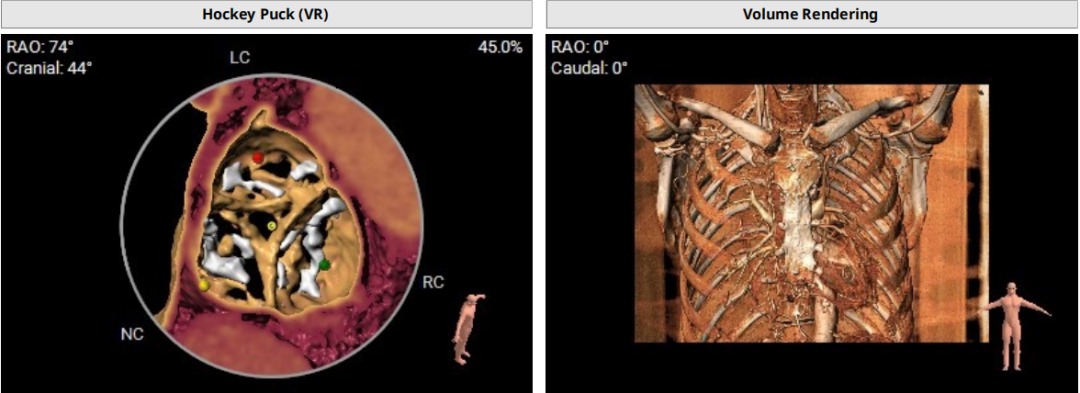

术前CT评估示

该患者升主动脉瓷化,左室流出道重度钙化。在TAVI手术过程中,导管和瓣膜的通过可能会对瓷化主动脉造成损伤,增加主动脉夹层、血管破裂等严重并发症风险;左室流出道的重度钙化会影响人工瓣膜与周围组织的贴合,使得瓣膜无法完全密封,从而增加瓣周漏的发生概率。

近日,中国人民解放军南部战区总医院王显悦教授、张本教授团队应用J-VALVE瓣膜完成一例高难度经心尖TAVI。患者为72岁男性,心脏超声示主动脉瓣重度狭窄伴轻度关闭不全,且二尖瓣中度狭窄。由于具有急性心力衰竭、高血压3级、肺气肿等其他疾病,且体重仅35公斤,对外科开胸手术耐受较差,风险极大,经过团队综合评估,决定行经心尖TAVI手术,拟植入25mm J-VALVE瓣膜。该患者存在升主动脉瓷化和左室流出道重度钙化,为手术增加了额外难度,术者团队凭借过硬的专业技能和细节处理能力,有效避免了术中可能存在的风险,并成功植入瓣膜。术后食道超声示无瓣周漏、无冠脉堵塞等并发症,患者症状明显缓解,手术顺利完成。